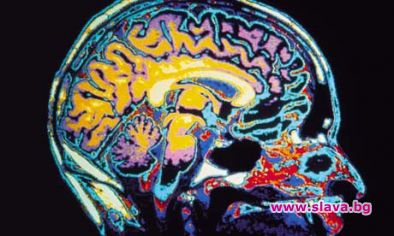

Учени от Калифорнийския университет Бъркли са разработили нов компютър, който може да чете мисли и да ги превръща в думи, съобщава БТА, цитирани от бТВ.

Новото изобретение за "декодиране на вътрешни гласове" ще предизвика революция в областта си, но най-вече ще бъде от голяма полза за пациентите, пострадали от инсулт и други дегенеративни заболявания засягащи речта.

Калифорнийският изследователски екип, ръководен от проф. Робърт Найт и проф. Брайън Пейсли, успя да реконструира някои думи въз основата на мозъчните вълни на пациенти, когато си мислят за тези словосъчетания. Учените са тествали 15 души, на които са им били направени операции на мозъка за лечение на епилепсии и тумори.

Те се съгласили да им бъдат поставени 256 електрода върху мозъчната кора, докато в същото време слушали съществителни, глаголи и имена. В същото време компютърна програма анализирала как мозъкът обработва и възпроизвежда чутите слова.

Компютър събирал цялата информация и възпроизвеждал по много подобен начин чутите думи от пациентите още от първия опит. Според проф. Пейсли възприятията и образите доста си приличат в човешкия мозък. В следващи опити екипът се надява записите на мозъчните вълни да му позволят да синтезира звука на човешката мисъл и тя да бъде изписвана от компютър чрез специален интерфейс.

Експериментите се оказали толкова успешни, че учените превръщали чрез компютъра в звук думите, за които си мислели пациентите и ги отгатвали.